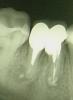

gorelovea Опубликовано 19 апреля, 2011 Поделиться Опубликовано 19 апреля, 2011 Пациентка С. 29 лет пришла с направлением на удаление 46 зуба. После консультации с ортопедом зуб решили сохранить.Перепломбировал корневые каналы, заапикально вывел "Vitapex" и запломбировал эндометазоном с гуттаперчей(на тот момент не было ни эндомотора, ни ультразвука).Далее провёл операцию премоляризации(разъединение), через 3-4 недели ортопед изготовил двевкладки и покрыл их металлокерамической коронкой.Через год сделали Rg-контроль. Зуб не беспокоил, в периапикальных тканях изменения уменьшались.Месяц назад сделали Rg-контроль(прошло 3 года). Зуб не беспокоит, в периапикальных тканях изменений нет. Ссылка на комментарий

Kivilgar Опубликовано 19 апреля, 2011 Поделиться Опубликовано 19 апреля, 2011 (изменено) Месяц назад сделали Rg-контроль(прошло 3 года). Зуб не беспокоит, в периапикальных тканях изменений нет. А мне видится, что патология в периапексе сохранена. И с костью вокруг корней проблемы. Все равно ждет удаление. Изменено 19 апреля, 2011 пользователем Kivilgar Ссылка на комментарий

pascal Опубликовано 21 апреля, 2011 Поделиться Опубликовано 21 апреля, 2011 А на втором снимке за верхушку эндометазон так выведен?? специально?? Почему имплант не захотели? Зубки три года то ещё простоят, но условия для адекватного протезирования уже уйдут Ссылка на комментарий

gorelovea Опубликовано 24 апреля, 2011 Автор Поделиться Опубликовано 24 апреля, 2011 А на втором снимке за верхушку эндометазон так выведен?? специально?? Почему имплант не захотели? Зубки три года то ещё простоят, но условия для адекватного протезирования уже уйдутЗаапикально выведен Vitapex. Ещё не известно сколько лет простоит имплант. А на тот момент у нас ставили только Новокузнецкие цилиндры с памятью формы. Ссылка на комментарий

pascal Опубликовано 25 апреля, 2011 Поделиться Опубликовано 25 апреля, 2011 Заапикально выведен Vitapex. Ещё не известно сколько лет простоит имплант. А на тот момент у нас ставили только Новокузнецкие цилиндры с памятью формы.Имплант простоит долго, просто надо иметь на примете хорошего имплантолога. И если даже у Вас ставят только Новокузнецк, направте в другой город , изготовив временную конструкцию например адгезивную. А так - вы старались, но очаги хронической инфекции остались, а в бифуркации даже увеличились. не надо эксперементировать, всё давно это до нас сделано Ссылка на комментарий

Каплан Опубликовано 5 февраля, 2014 Поделиться Опубликовано 5 февраля, 2014 Заапикально то зачем? Стечение обстоятельств или намеренно?Игорь, я думаю мы теперь никогда об этом не узнаем. А вообще, последняя манипуляция, которую я бы делал. Тут вообще очень показательно. За 3 года кость убежала по фуркации Ссылка на комментарий

Kolchanov Опубликовано 5 февраля, 2014 Поделиться Опубликовано 5 февраля, 2014 Прикольный случай какой! Только надо, чтобы ортопеды из ГОСа не видели У нас любят подобную х-ню восстанавливать. Жаль, что автор давно не появляется на форуме. Было бы интересно увидеть продолжение. За 3 года кость убежала по фуркации На биологическую ширину убежала. 2 Ссылка на комментарий